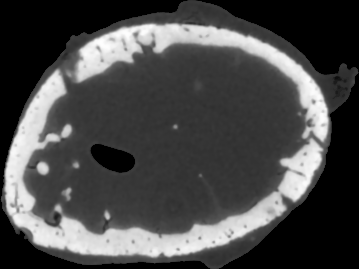

To simulate emission tomography reconstruction we designed a more realistic phantom from the high-quality X-ray scan of a mice bone. The data was acquired on a Nikon Metris Custom Bay cone-beam scanner at the Henry Moseley Manchester X-ray facility, and was reconstructed with the Feldkamp algorithm (see Fig. 7 (left)). We thresholded the obtained reconstruction and added six gaussians with various kernel widths (see Fig. 7 (middle and right)).

To simulate PET projection data we used NiftyRec [22], a software for tomographic reconstruction, providing GPU-accelerated reconstruction for emission and transmission computed tomography. The phantom size is pixels and 300 projections was simulated. Poisson noise was added to projections with an expected number of photon counts in total. Twenty noise realizations were simulated to estimate methods quantitatively. The point spread function of the PET system was modelled (with convolution of the sinogram columns with a Gaussian of full width half maximum of three pixels) in the projection and back-projection operations. No scatter was simulated in this study. For our experiments (see algorithm 2) we performed 130 MLEM iterations and 5 inner iterations (denoising step).

In Fig. 10 and 11 one can notice that the BR is very smooth for TV and TV- penalties and some long-wave oscillations can be seen in the reconstructed image with EL penalty. This result corresponds to the expected behaviour of the EL penalty. We note here that the phantoms background (see Fig. 7) is not as flat as TV and TV- penalty recovered it. Furthermore, a small size dot-like feature (approximately in the centre of the phantom) is almost smoothed out with TV and TV- recovery. However, it is visible and well recovered with EL penalty. The sharp features, overall, are reconstructed very well with MLEM-EL method and seem even sharper compare to other methods (see the bone outer rim in Fig 10).